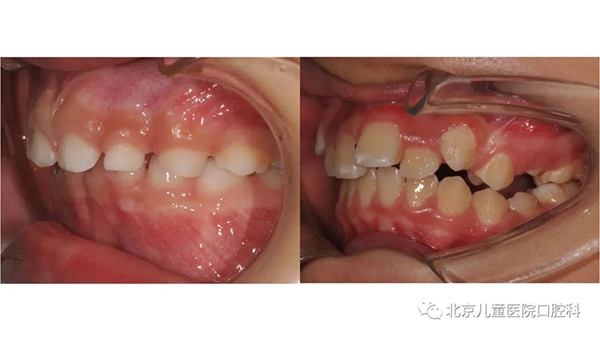

错颌畸形:引起错颌畸形的众多原因中,包括先天遗传和口腔不良习惯等。奶瓶戒断时间过晚、咬嘴唇、张口呼吸、吐舌头、偏侧咀嚼等行为都会对牙齿和颌骨的生长发育造成不良影响。比如反合、开合、上牙前突,小下颌、面部不对称等。